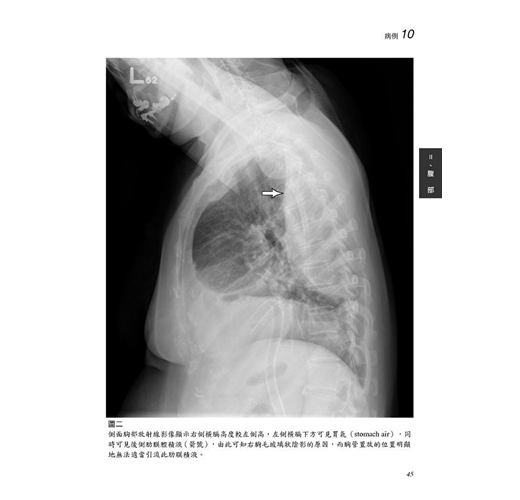

病例10 胸管錯置放(Malposition of chest tube) 44

病例11 橫膈疝氣(Diaphragmatic hernia) 49